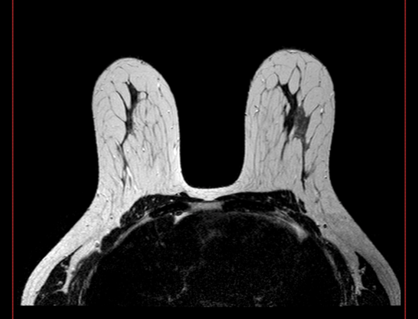

Standardized body region labelling of individual images provides data that can improve human and computer use of medical images. A CNN-based classifier was developed to identify body regions in CT and MRI. 17 CT (18 MRI) body regions covering the entire human body were defined for the classification task. Three retrospective databases were built for the AI model training, validation, and testing, with a balanced distribution of studies per body region. The test databases originated from a different healthcare network. Accuracy, recall and precision of the classifier was evaluated for patient age, patient gender, institution, scanner manufacturer, contrast, slice thickness, MRI sequence, and CT kernel. The data included a retrospective cohort of 2,934 anonymized CT cases (training: 1,804 studies, validation: 602 studies, test: 528 studies) and 3,185 anonymized MRI cases (training: 1,911 studies, validation: 636 studies, test: 638 studies). 27 institutions from primary care hospitals, community hospitals and imaging centers contributed to the test datasets. The data included cases of all genders in equal proportions and subjects aged from a few months old to +90 years old. An image-level prediction accuracy of 91.9% (90.2 - 92.1) for CT, and 94.2% (92.0 - 95.6) for MRI was achieved. The classification results were robust across all body regions and confounding factors. Due to limited data, performance results for subjects under 10 years-old could not be reliably evaluated. We show that deep learning models can classify CT and MRI images by body region including lower and upper extremities with high accuracy.